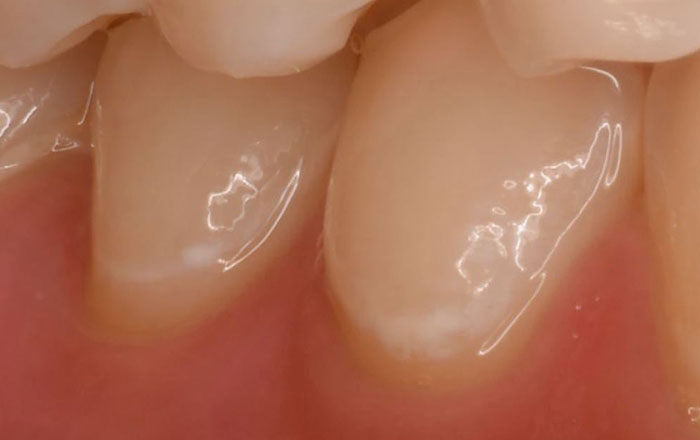

特に、下記の画像のような初期のむし歯(CO)の状態は、歯の表面が溶けてしまっているので、健康な歯とは色が違って歯の一部が白濁していますが、まだ歯に穴は空いていない状態です。

この状態の歯にフッ化物(フッ素)を使うことで、再石灰化が行われ、歯から溶け出したカルシウムやリンを歯の表面に戻し、歯を修復する働きがあります。